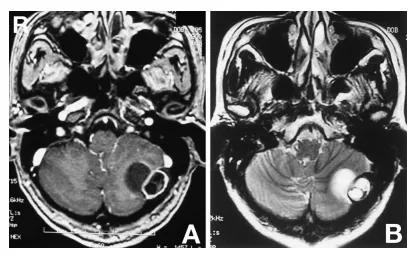

计算机断层扫描(CT)显示左侧后颅窝内板处存在伴钙化的低密度肿块(图2A)。骨窗CT显示颅骨内板受侵蚀(图2B)。钆增强T1加权磁共振成像显示板障内部分呈低信号伴环形强化,小脑内部分呈低信号(图3A)。T2加权磁共振成像显示硬膜外部分呈高信号,硬膜下部分呈高信号并延伸至小脑(图3B)。